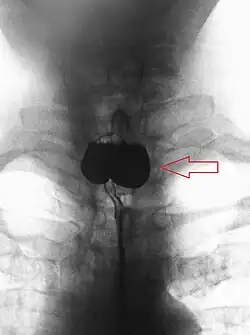

Le diagnostic est radiologique. Aujourd'hui l'imagerie de première intention à effectuer est un scanner cervico-thoraco-abdomino-pelvien avec opacification digestive haute ainsi qu'injection de produit de contraste. Le transit œso-gastro-duodénal historiquement utilisé qui visualise le diverticule sous forme d'une image d'addition du tiers supérieur de l'œsophage n'a pratiquement plus d'indication à l'heure actuelle en raison de la meilleure précision de l'examen TDM[1].